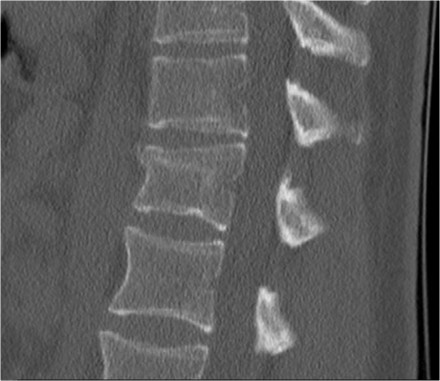

Rigid spine

Patients with a rigid spine (such as in ankylosing spondylitis, DISH and rheumatoid arthritis) are more susceptible to spinal fractures, even after minimal trauma (6).

Ossification of the spinal ligaments and calcification of the annulus fibrosus alter the biomechanics of the spine, creating long lever arms and limiting the ability to absorb even minor impacts.

The bone is usually very osteoporotic.

The images are of a patient with a typical bamboo spine as a result of ankylosing spondylitis.

After a fall on his back no fracture was seen on the x-rays.

However the CT shows a thin fracture line through the anterior side of the vertebral body and also through the spinous process.